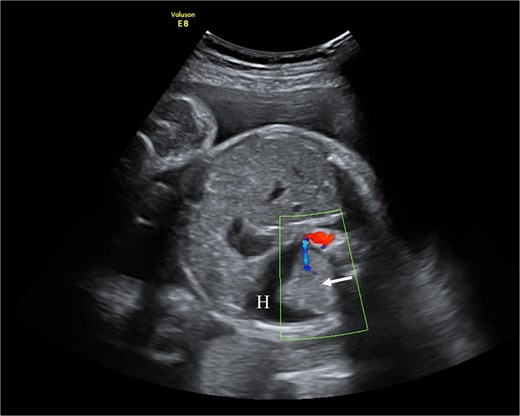

A 22-year-old primigravida was referred at 29 + 4 weeks due to abnormal fetal sonography showing a left supradiaphragmatic mass, hydrothorax, and rightward heart displacement. Magnetic resonance imaging (MRI) revealed a 2.6 × 1.9 × 1.6 cm supradiaphragmatic structure with an aortic arterial supply, confirming PS.

At 31 + 5 weeks, worsening hydrothorax prompted initiation of pulmonary maturation (Fig. 1). One week later, ultrasound showed bilateral hydrothorax compressing both lungs, dextrocardia, and hydrocele, indicating impending hydrops. A multidisciplinary team decided on EXIT to alleviate lung compression and facilitate breathing before cord clamping.

Fetal ultrasound with doppler. The arrow points to PS having a separate feeding branch from the aorta. Around sequestration the hydrothorax is present (H).